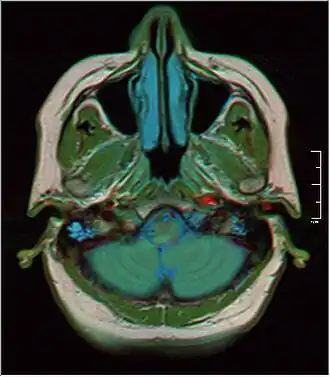

MRI showing fluid in mastoid air cells | |

The mastoid cells (also called air cells of Lenoir or mastoid cells of Lenoir) are air-filled cavities within the mastoid process of the temporal bone of the cranium. The mastoid cells are a form of skeletal pneumaticity. Infection in these cells is called mastoiditis.

Clinical significance

Infections in the middle ear easily spread into the mastoid air cells through the aditus ad antrum, resulting in mastoiditis, a potentially dangerous and life-threatening condition. Infection may then further spread into the middle cranial fossa or posterior cranial fossa, causing meningitis or abscess of adjacent brain tissue. Infection may also spread to muscles of the neck, causing pain and torticollis.[1]: 746